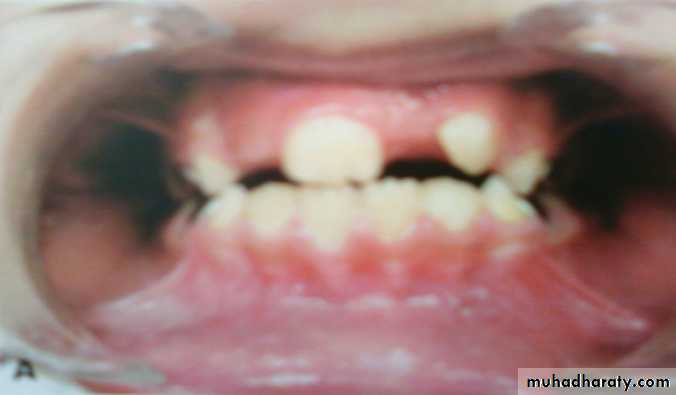

50a) Physiologic median diastema/ ugly duckling stage

It is a transient or self correcting malocclusion which is seen in the maxillary incisor region between 8-9 years. It is particularly seen during the eruption of the permanent canines.